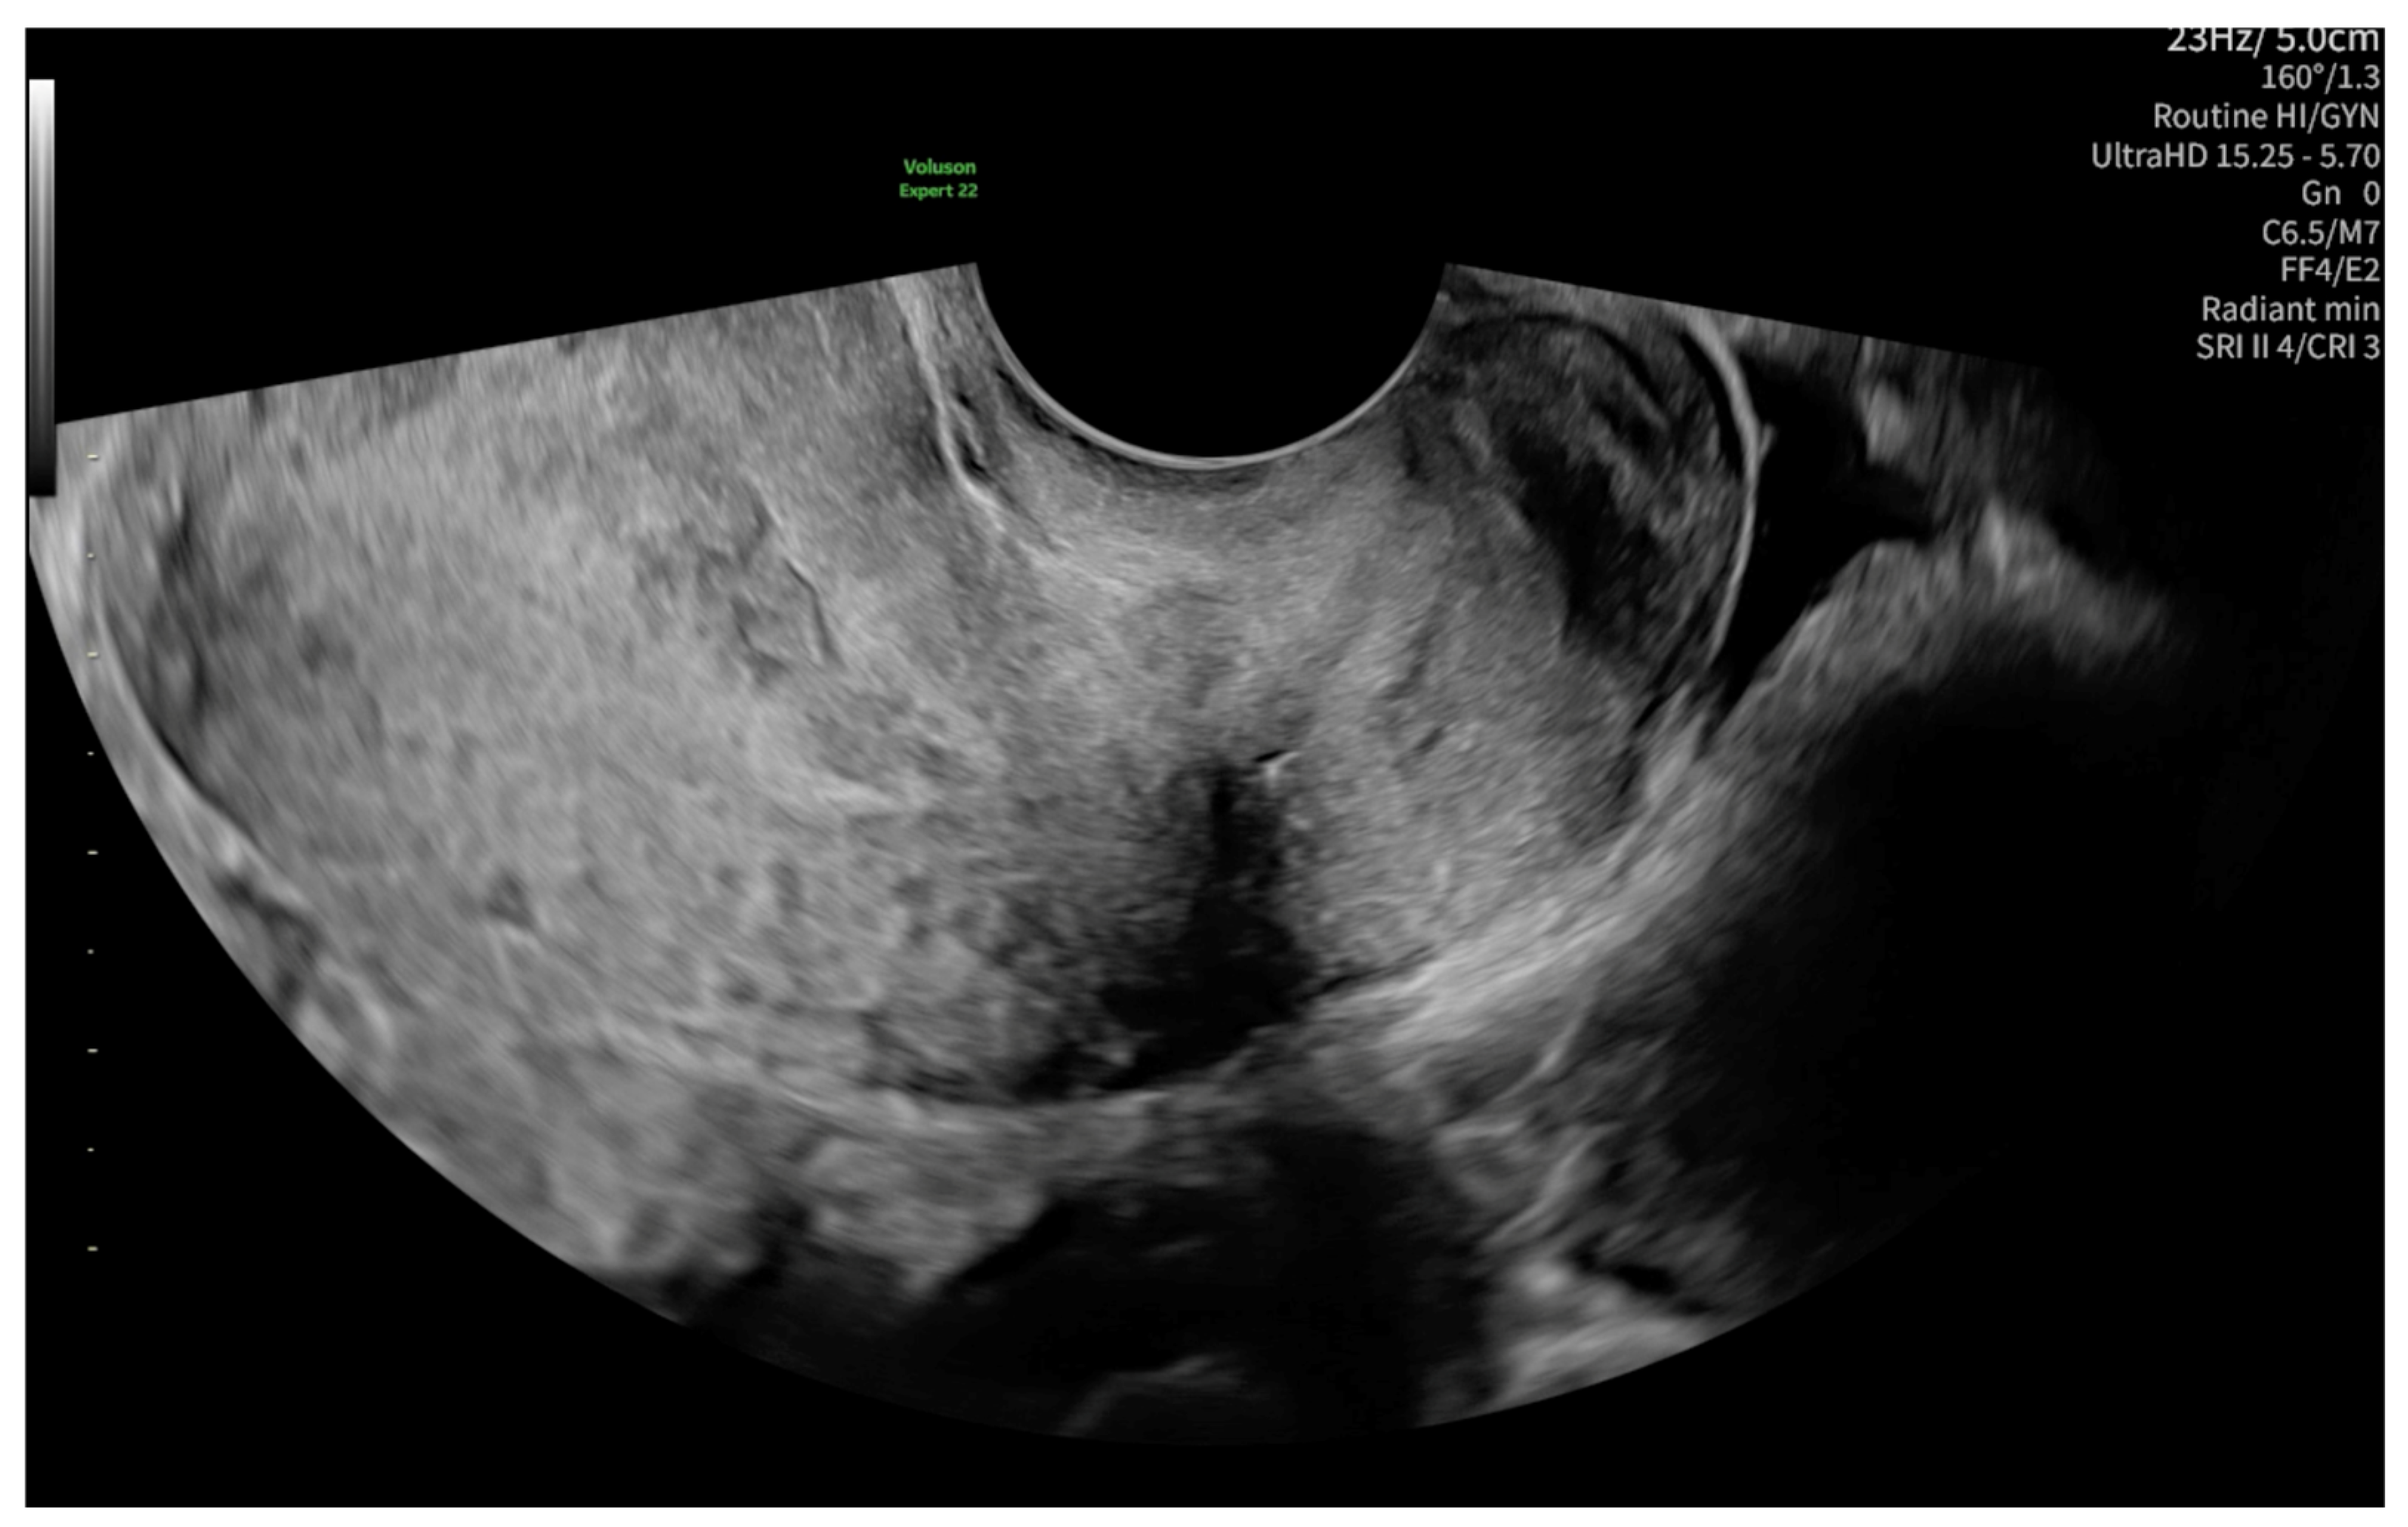

2. Case Presentation